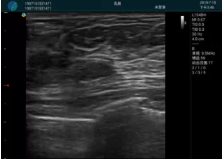

腺體內(nèi)部清晰顯示一低回聲塊影,形態(tài)不規(guī)則,邊界模糊,邊緣呈毛刺狀,內(nèi)部見砂礫樣鈣化

M20引導(dǎo)下穿刺活檢術(shù)

M20引導(dǎo)下平面內(nèi)穿刺取出的腫塊組織